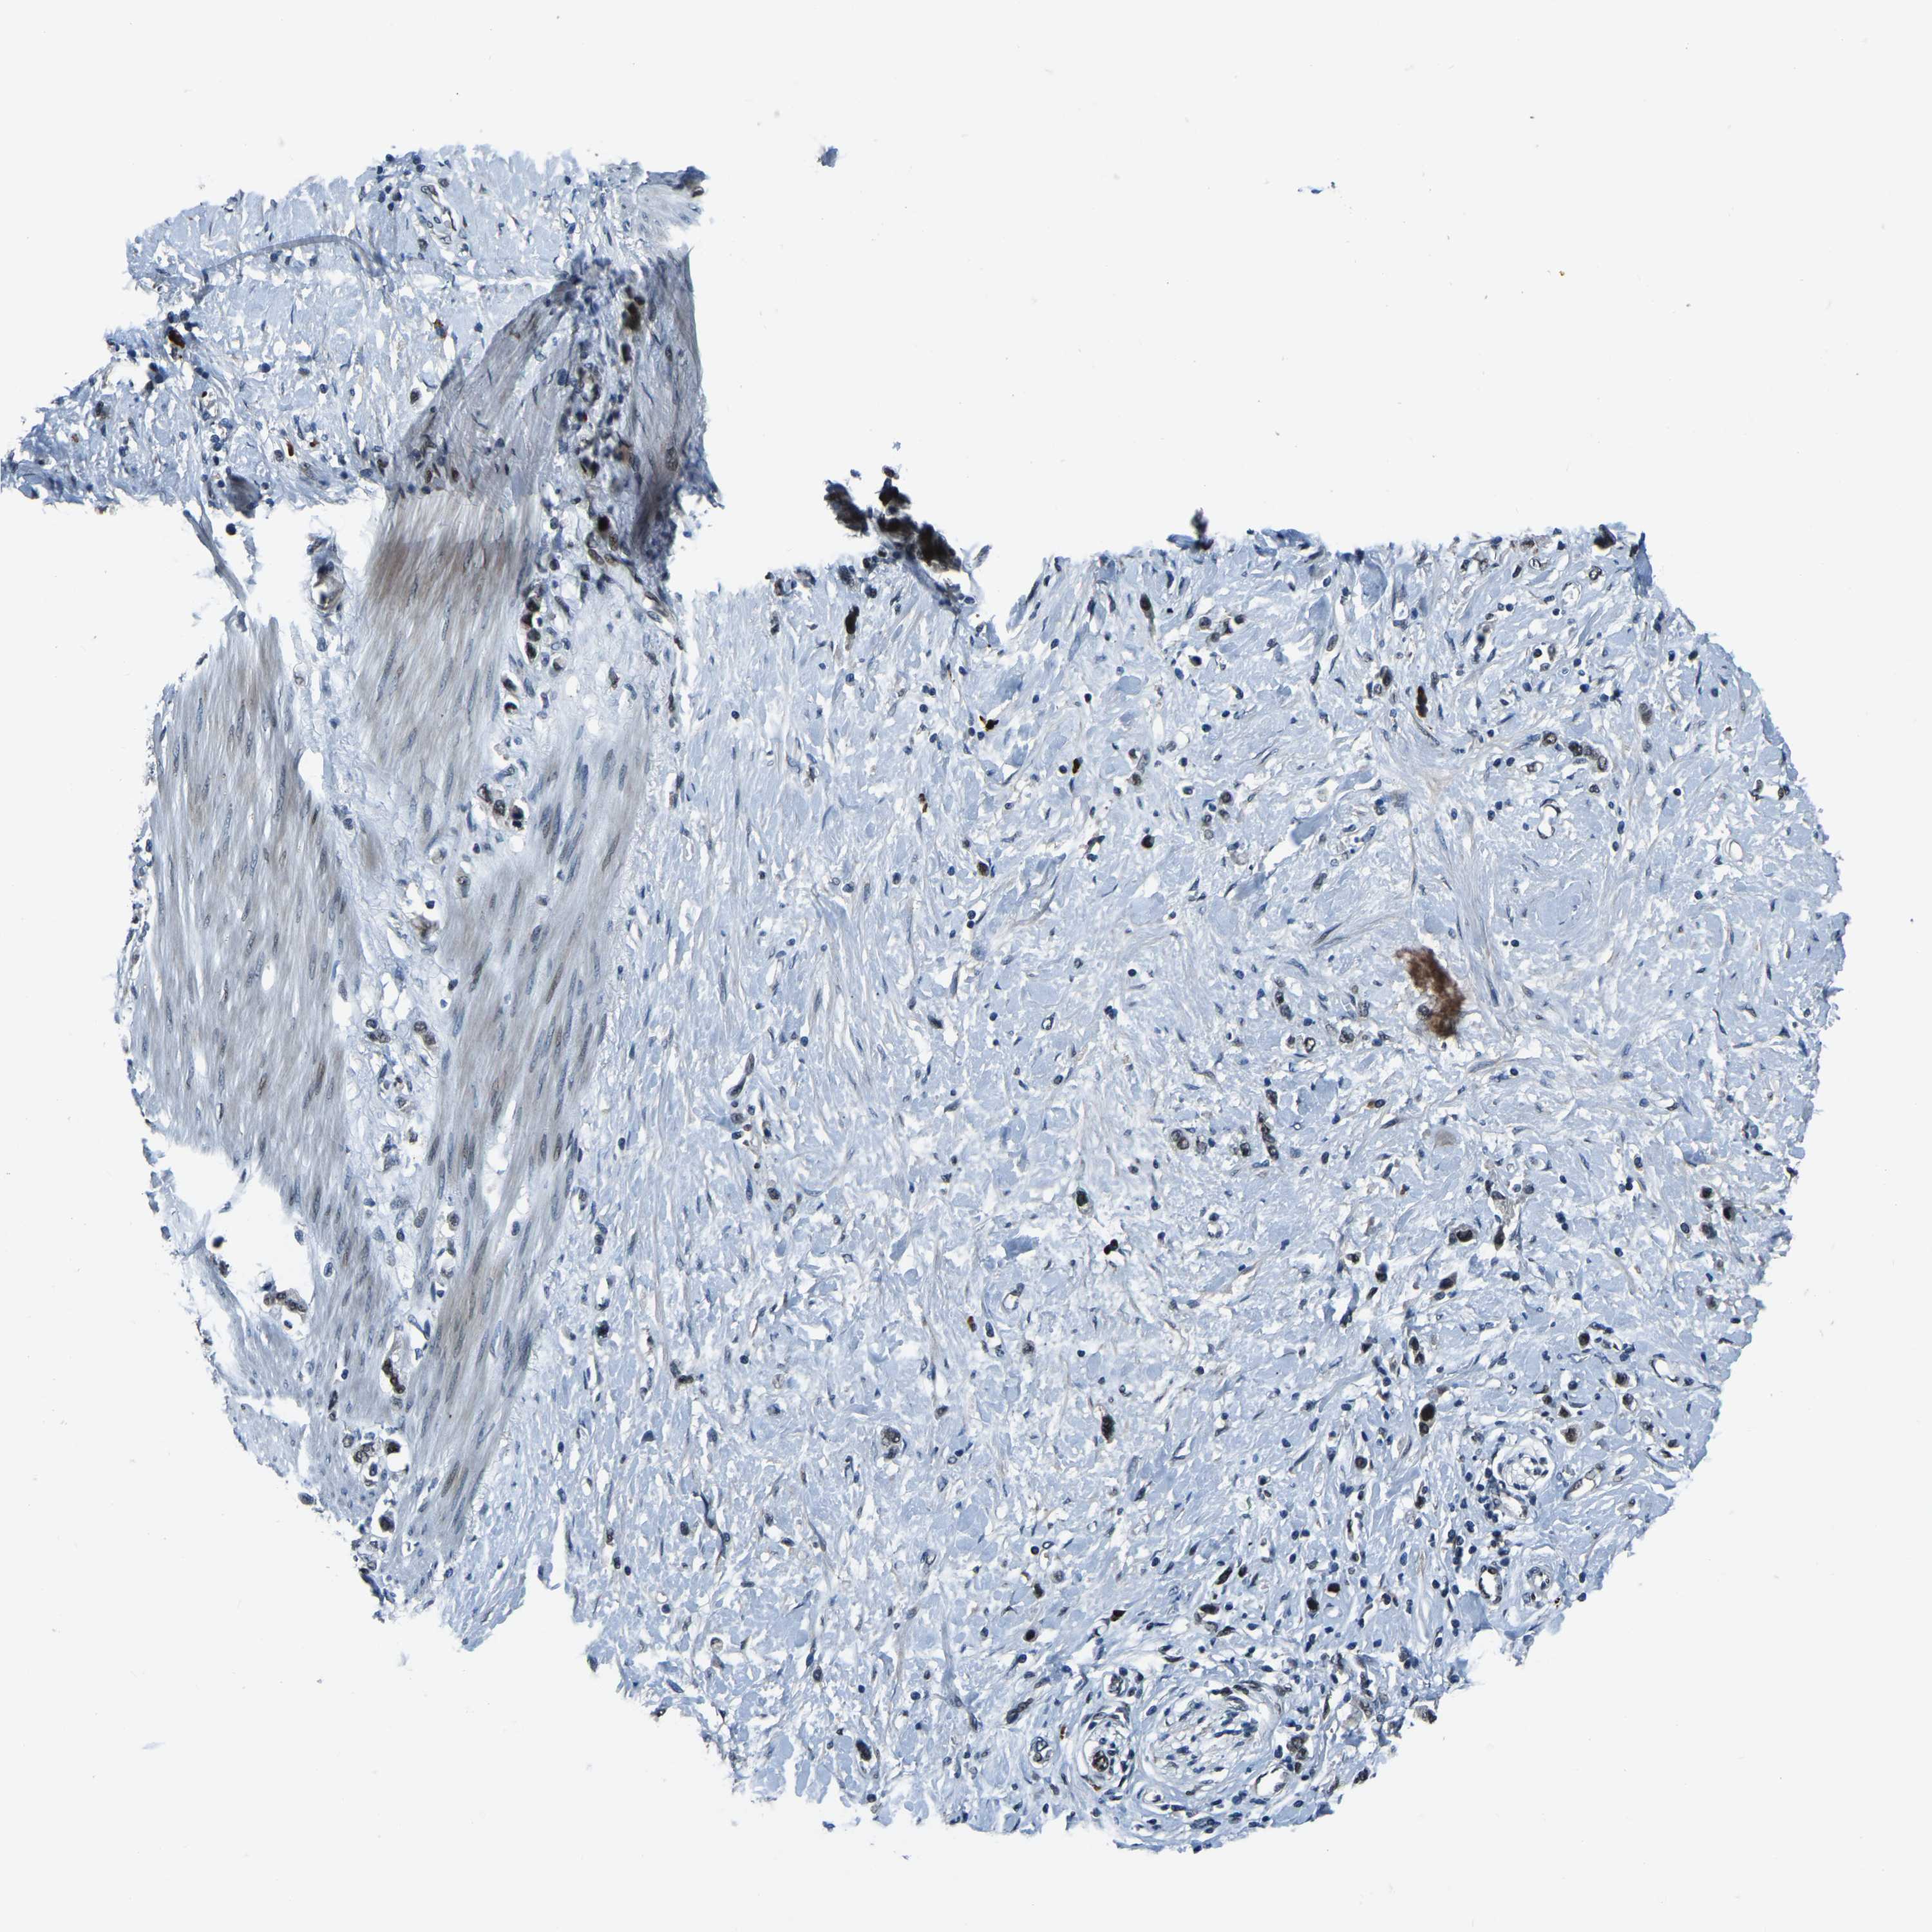

STOMACH CANCER - Protein expressioni

A mouse-over function shows sample information and annotation data. Click on an image to view it in a full screen mode. Samples can be filtered based on level of antibody staining by selecting one or several of the following categories: high, medium, low and not detected. The assay and annotation is described here.

Antibody stainingi

Antibody staining in the annotated cell types in the current human tissue is reported as not detected, low, medium, or high, based on conventional immunohistochemistry profiling in selected tissues. This score is based on the combination of the staining intensity and fraction of stained cells.

Each image is clickable and will lead to virtual microscopy that enables deeper exploration of all samples and also displays staining intensity scores, fraction scores and subcellular localization as well as patient and tissue information for each sample.

Antibody HPA019486

Antibody HPA021517

Staining

High

Medium

Low

Not detected

Intensity

Strong

Moderate

Weak

Negative

Quantity

>75%

75%-25%

<25%

None

Location

Nuclear

Cytoplasmic/membranous

Cytoplasmic/membranous,nuclear

Adenocarcinoma, NOS